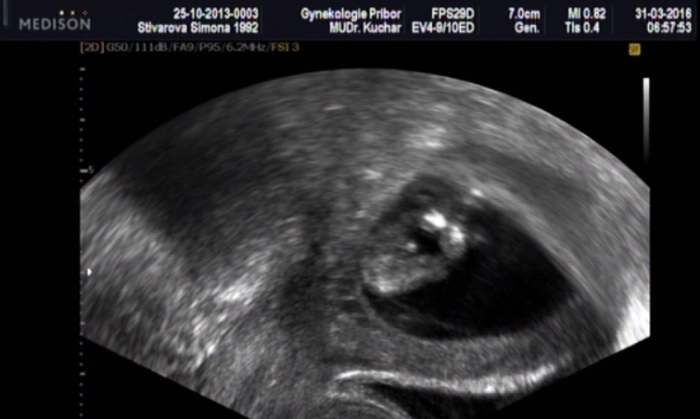

[883491]ja tam teda nevidim vubec nic,ani samotne mimi zda tam teda je vubec zabrane cele

[883496] nee to je jen kousííček právě s pindííkem nejspíše :D mám natočené video tak jsem to pauzla a udělala print screen :)